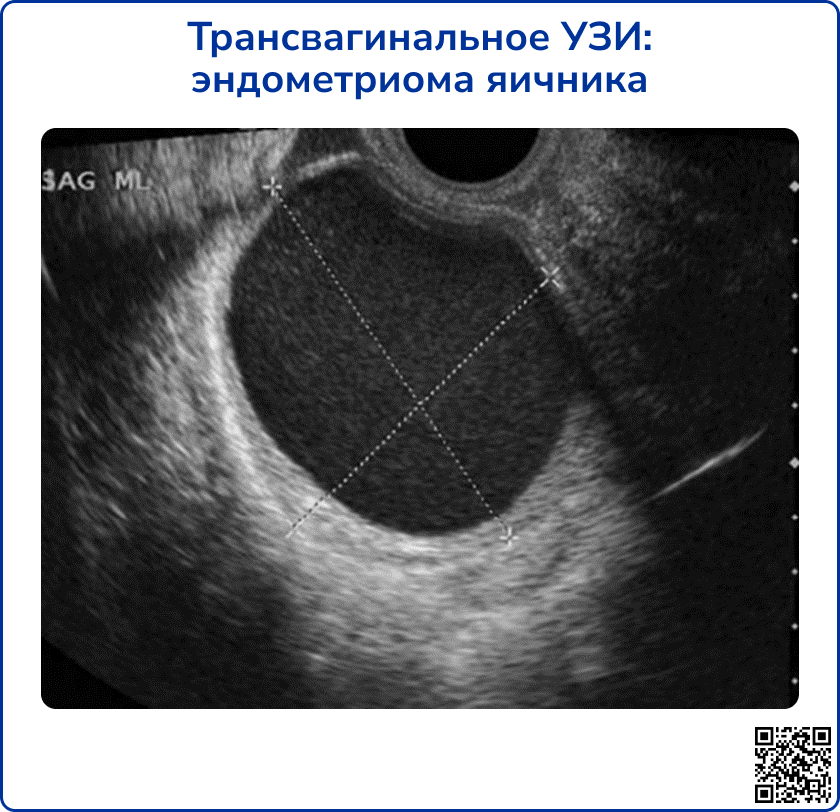

Наиболее информативно трансвагинальное УЗИ. При обследовании женщин, не живущих половой жизнью, возможно трансабдоминальное и трансректальное исследование.

Типичная эндометриоидная киста представляет собой округлое образование с ровным контуром и однородным гипоэхогенным содержимым, вид которого иногда характеризуют как “матовое стекло”. При цветном допплеровском картировании может визуализироваться периферический кровоток, но отсутствует васкуляризация внутри кисты. Возможно небольшое количество (до 4-х) тонких перегородок внутри кисты. Реже встречаются эндометриомы с толстыми септами и выраженной капсулой. У женщин в постменопаузе эндометриомы значительно чаще бывают многокамерными, чем в репродуктивном возрасте [9].